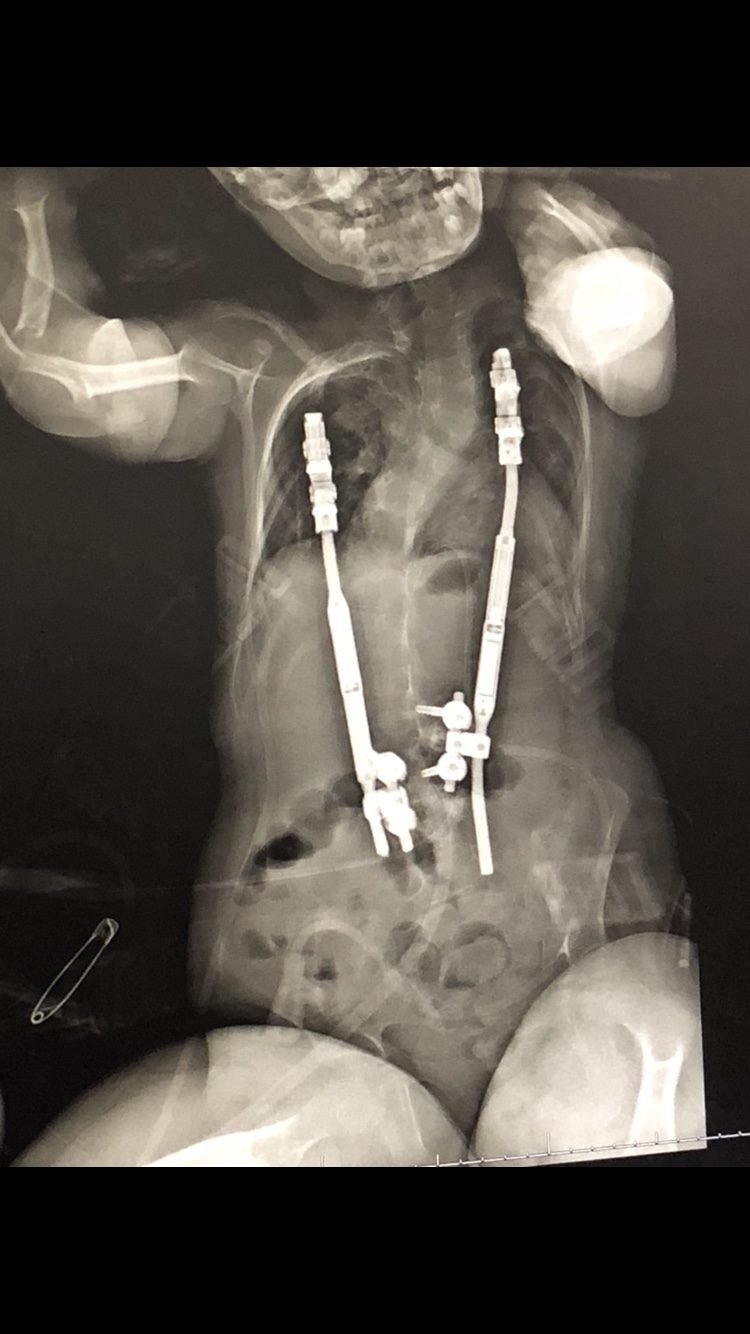

Traditional Growing Rods (TGR):

TGR attach below and above the spinal curve.

Vertical Expandable Prosthetic Titanium Rib (VEPTR):

The Vertical Expandable Prosthetic Titanium Rib is a curved metal rod surgically attached to a child’s rib, spine, or pelvis using hooks on both ends. VEPTR’s separate the rib and straighten the spine, allowing their lungs to grow with the child.

MAGnetic Expansion Control System (MAGEC):

The MAGnetic Expansion Control System includes implantable rods that allow non-invasive expansions. However, young children with severe or stiff spinal deformities do not benefit from MAGEC rods. Ultimately, surgeons rarely perform conversion operations (removing TGR/VEPTR and exchanging with MAGEC) due to the magnetic growing rods not being strong enough.